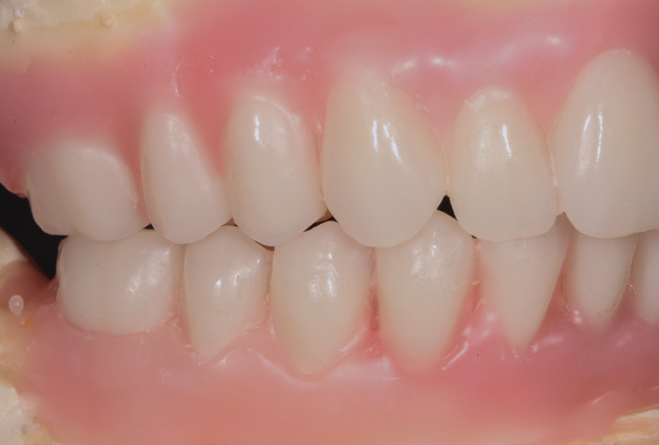

Fig 18. The patient’s intraoral condition.

Figure 18

Fig 19. Patient smile shown 3 years post-treatment.

Figure 19

Fig 20. Patient intraoral condition 3 years following delivery of maxillary and mandibular All-on-4 definitive prosthesis.

Figure 20